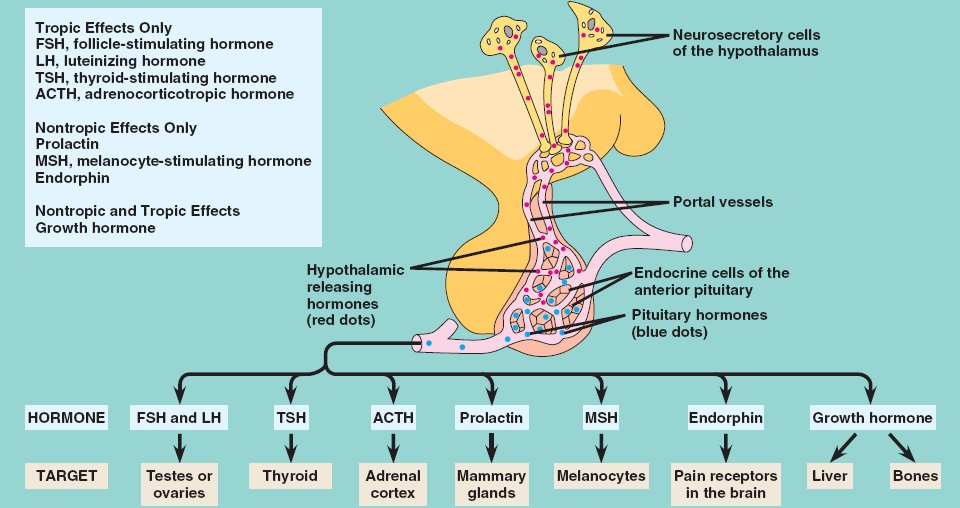

45_08AntPituitaryHormones

adenohypophysis.html